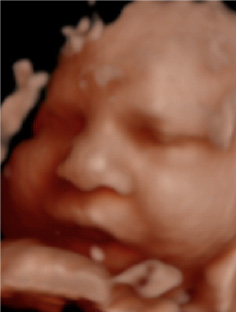

Experimenta la última tecnología hiperrealista 8K, una imagen increíblemente detallada y realista de los rasgos de tu bebé, con una textura y definición que te sorprenderán.

Ecox Alicante ya cuenta con la posibilidad de ofrecer a todos los futuros papis madrileños una experiencia inolvidable gracias a la ecografía 5D y el novedoso hiperrealismo 8K.

Esta nueva tecnología nos permite ofreceros a los futuros papás las imágenes de mayor calidad para que disfrutéis de la experiencia como nunca antes había sido posible.